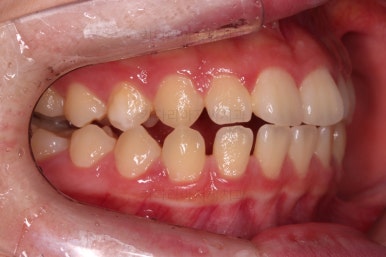

동래교정치과 초진 시 입안의 모습입니다.

치아가 벌어진 것도 벌어진 것이지만 교합이 전혀 안되고 있었어요.

틈새도 아랫니에 훨씬 많았고요.

윗니가 있는 위턱뼈가 전반적으로 아래턱에 비해 3차원으로 작은 양상이었습니다.

이번 환자분은 아랫니가 전반적으로 앞이든, 뒤든, 양옆으로든 넓어져 있는 양상이었고 그래서 아랫니에 틈도 많고 아래 앞니도 밀려나와 있는 양상인거죠.